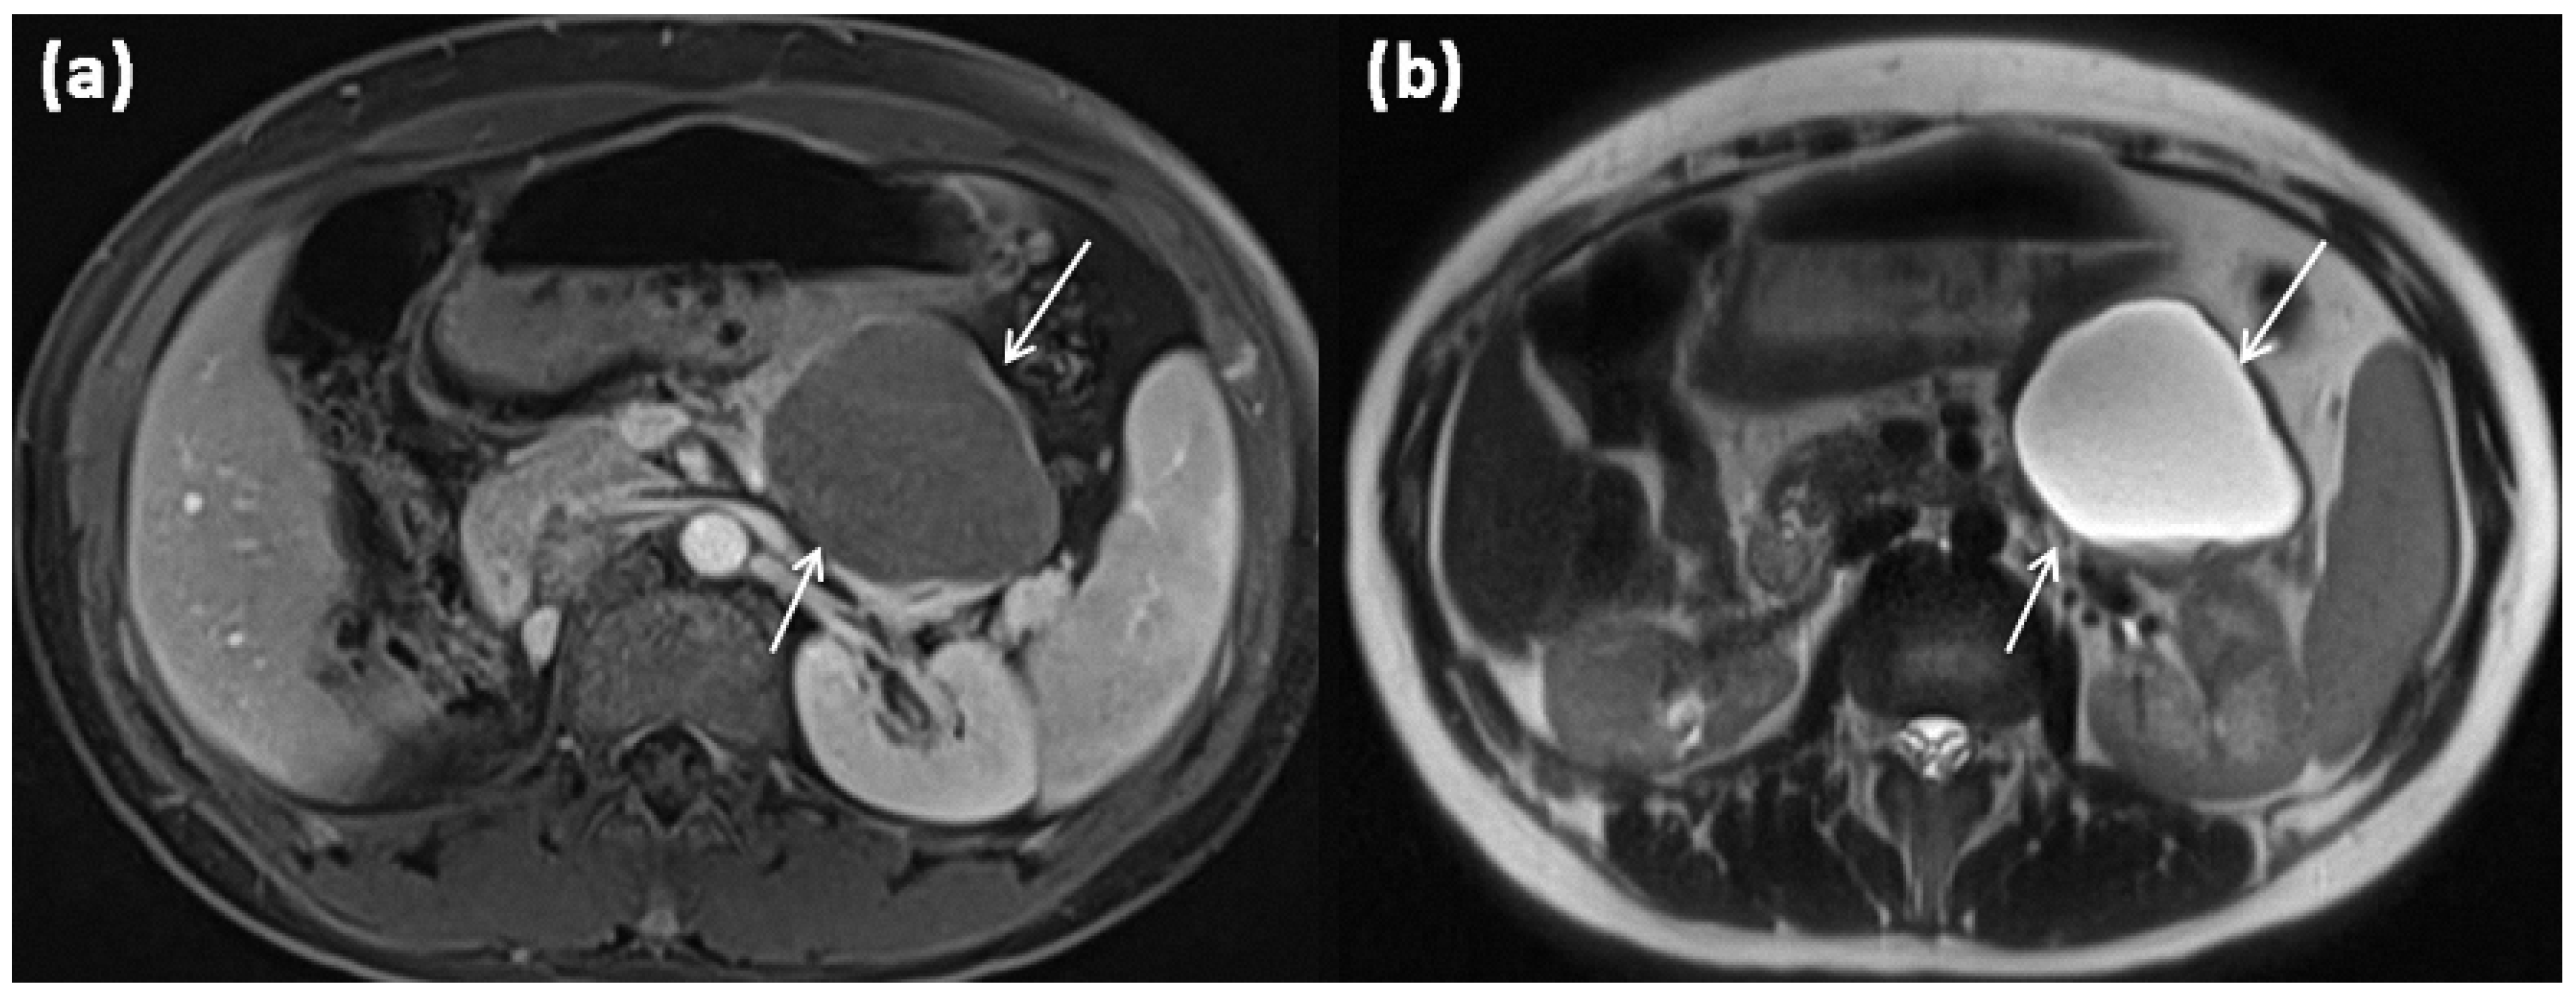

Figure 5.

MRI of a 67-year-old female patient with T1w sequence after gadolinium-based contrast administration (a) and T2w sequence (b). A large multicystic mass of the pancreatic tail (arrows) with tiny septa in T2w, as well as mild contrast enhancement of each septa, is seen.

The often thick cyst walls are well-demarcated in any cross-sectional imaging. MRI usually shows a macrocystic mass, which is usually composed of individual parts often exceeding 2 cm []. The cyst content, typically with a T2w hyperintense signal, may be aqueous, but may likewise be hemorrhagic or have varying protein concentrations with varying degrees of thickening. Therefore, in CT, higher HU values, and in MRI, the variability of native T1 and T2 signals, can be observed. After contrast application, an enhancement of the cyst wall, as well as of the septations, is seen []. In this context, especially in dynamic MRI sequences, an enhancement can be observed, particularly in the later phases due to the fibrous cyst walls; in addition, small mural nodules are possible [,,]. MRCP is mainly used for the differential diagnostic exclusion of a ductal connection, which is not present in MCN.

Peripheral eggshell-like calcifications, which are described as pathognomonic, are rare overall [], but are easier to detect using CT and are considered to be a criterion for a potentially malignant transformation, especially in the case of new occurrence or particularly strong or widely peripheral manifestation []. An occurrence at an older age is suspicious for malignancy as well as large individual cysts of more than 6 cm and irregular and very thick cyst walls with papillary projections in the sense of solid nodular components or hypervascular areas [,,,].